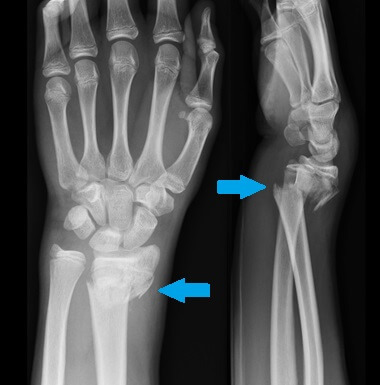

Describe Barton fracture?

DORSAL BARTON = usual

- Oblique intraarticular fracture of the dorsal rim of the distal radius with displacement of the carpus along with the fracture fragment

- Results from high-velocity impact across the articular surface of the radiocarpal joint, with the wrist in dorsiflexion at the moment of impact

VOLAR /REVERSE BARTON = rarer

- Wedge-shaped articular fragment sheared off the volar surface of the radius (volar rim fracture), displaced volarly along with the carpus

- Wrist in volar flexion at time of injury; also referred to as reverse Barton’s fracture; much rarer than dorsal Barton fracture